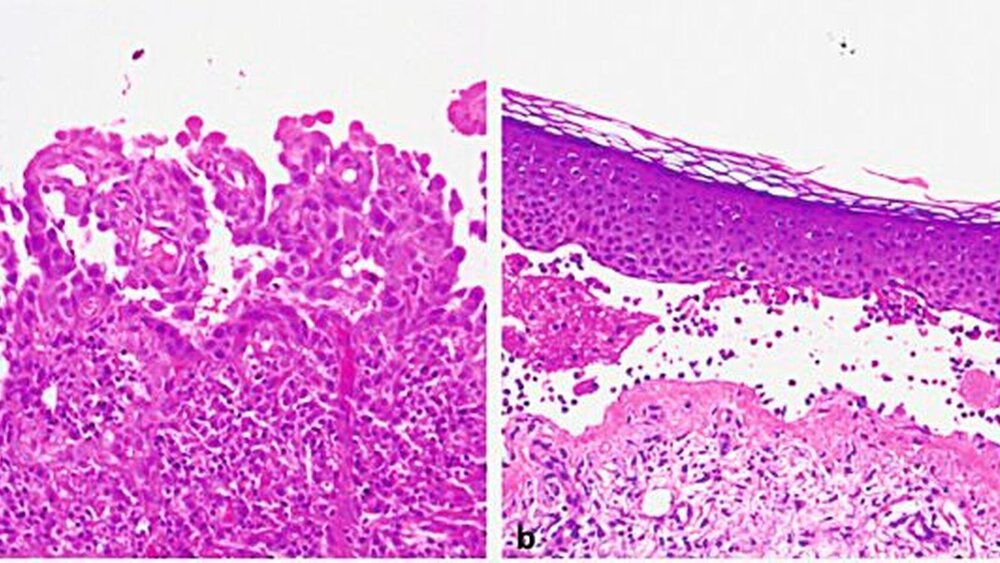

Durch die histologische Untersuchung einer läsionalen Probebiopsie kann man die Ebene der Spaltbildung identifizieren. Die histologische Untersuchung erfolgt mittels einfacher Hämatoxylin-Eosin (HE)-Färbung. Die Pemphiguserkrankungen zeigen eine intraepidermale Spaltbildung und Akantholyse (Abbildung 7a), während die Pemphigoiderkrankungen eine subepidermale Spaltbildung (Abbildung 7b) aufweisen. Eine sichere Differenzierung zwischen den verschiedenen Pemphigoiderkrankungen ist allein anhand der histopathologischen Untersuchung nicht möglich [Schmidt und Zillikens, 2016]. Die Histologie ist vor allem dann hilfreich, wenn die direkte IF sowie die serologische Untersuchung negativ sind, eine bullöse AID daher nicht vorliegt und Differenzialdiagnosen erwogen werden müssen (siehe unten).